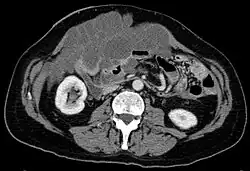

Im Ultraschallbild (Sonografie) zeigt sich eine echofreie, intraperitoneale, schleimige Masse in der gesamten Bauchhöhle und zwischen den Darmschlingen, in die charakteristische, zarte, streifige Reflexe eingelagert sind. Die Gallerte ist beweglich und verformbar, reagiert aber träger als ein klassischer Aszites. Aufgrund der Zähflüssigkeit zeigen sich groteske, tumorartige Formen.[4] Eine Computertomographie zeigt die Ausdehnung des Pseudomyxoms. In Abhängigkeit von der Ausdehnung sind eventuell zusätzlich endoskopische Untersuchungen von Magen oder Dickdarm, wie Darm- und Magenspiegelung, urologische Untersuchungen oder auch Untersuchungen von Herz und Lunge sowie Blutentnahmen nötig.[2] Als entscheidendes diagnostisches Merkmal gilt die extrazelluläre Schleimproduktion in der Bauchhöhle.[1]